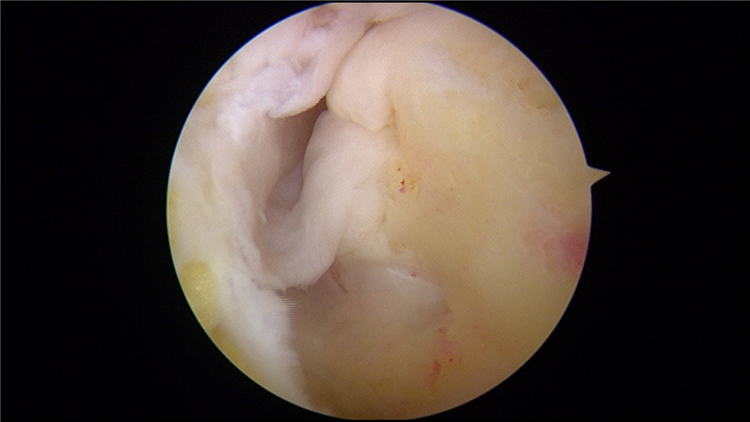

踝关节镜下的病灶局部踝关节镜下骨髓刺激术